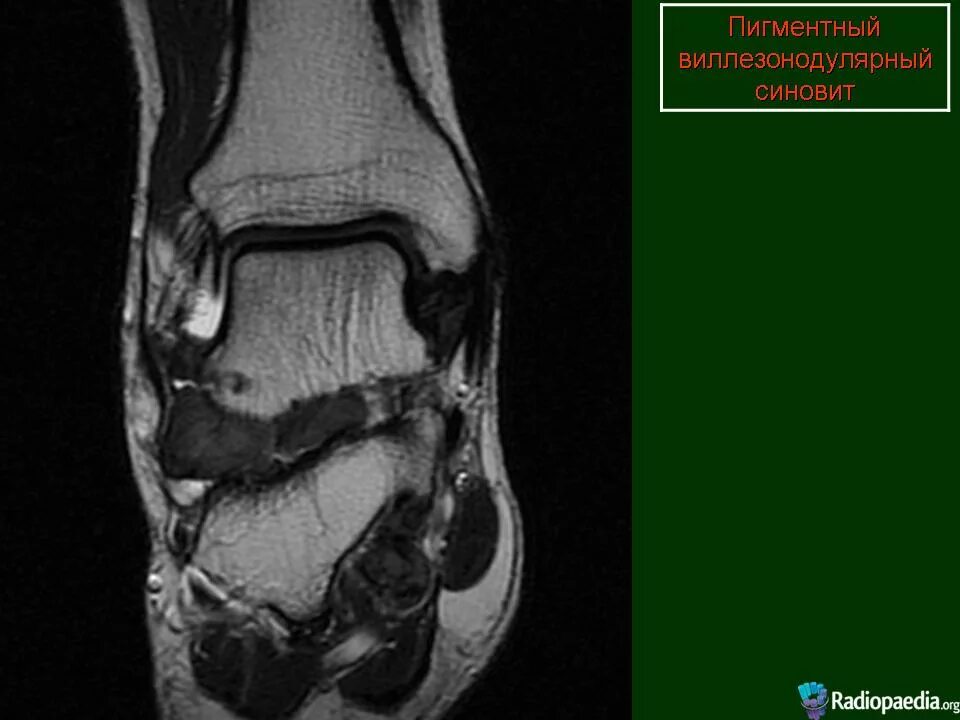

Пигментный виллонодулярный синовит